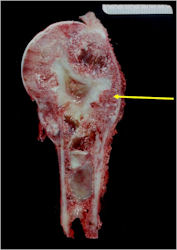

Gross Pathology

- Intraosseous component

- Firm, grey-white, moist, and glistening

- Extraosseous component

- Softer and more friable

- Hemorrhagic and cystic degeneration may be present in either location

- Diffuse involvement of the medullary cavity is often obvious